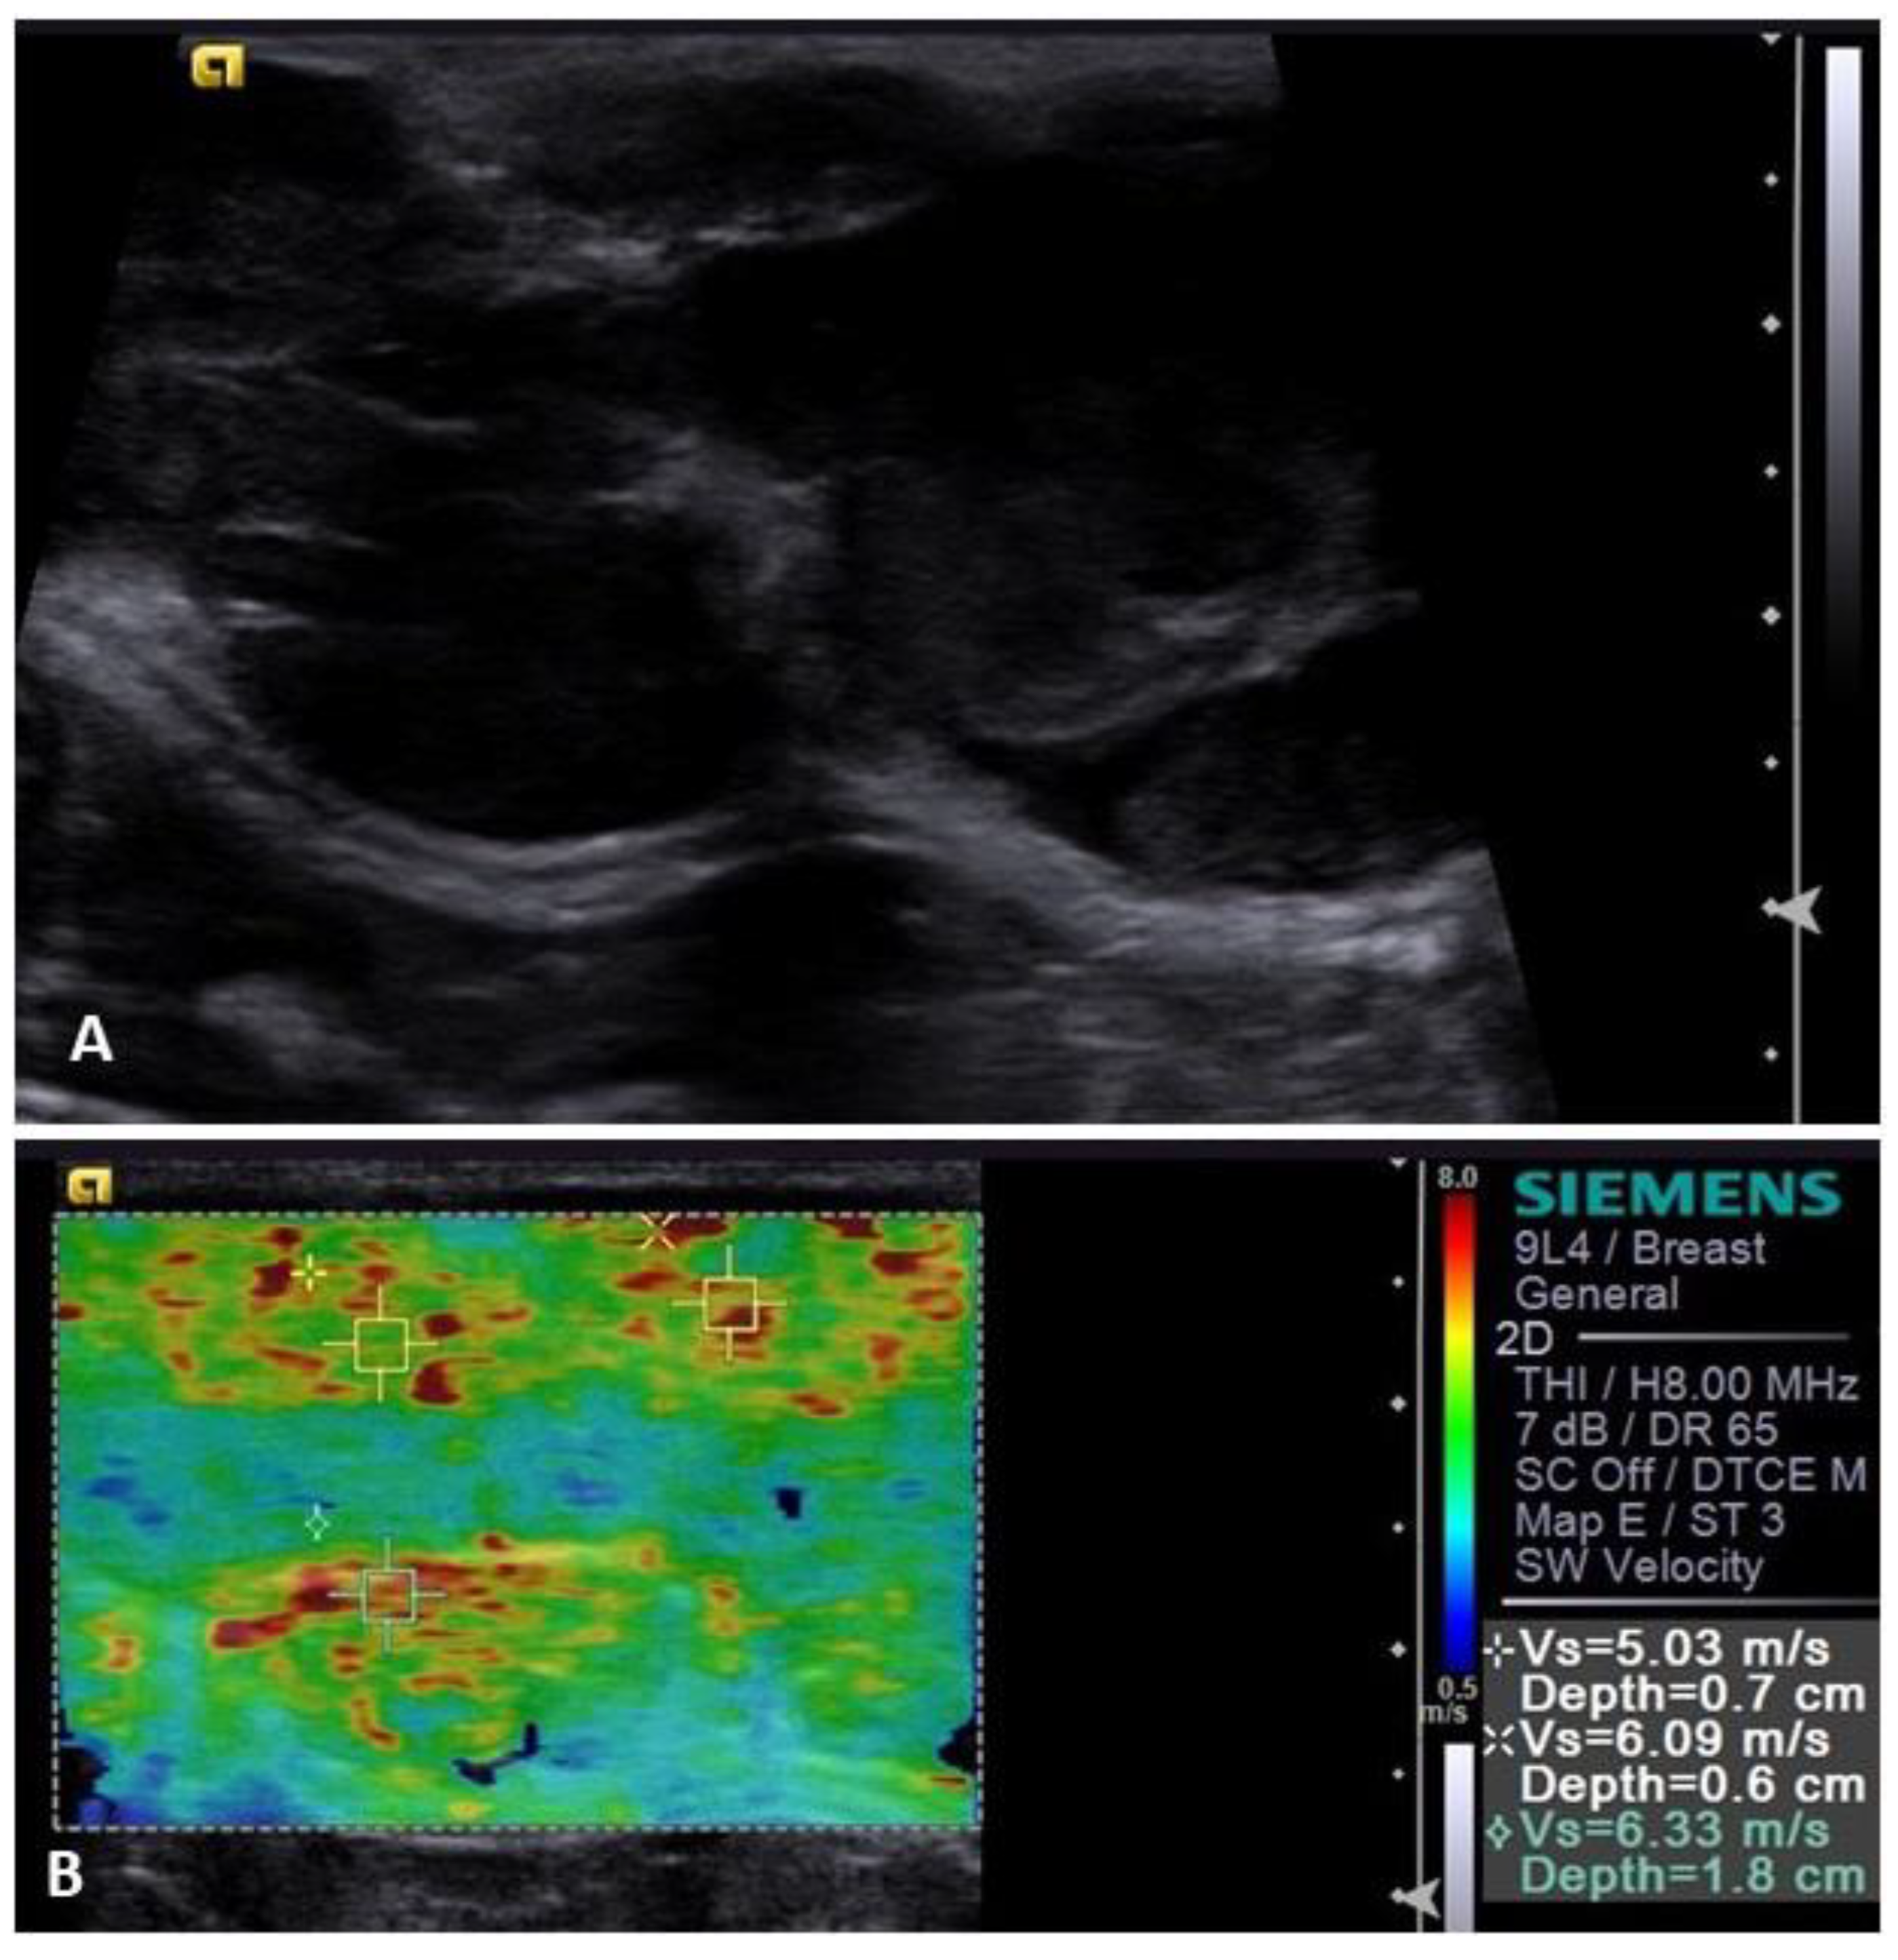

3.3. Elastography

- Massimini, M.; Gloria, A.; Romanucci, M.; Della Salda, L.; Di Francesco, L.; Contri, A. Strain and Shear-Wave Elastography and Their Relationship to Histopathological Features of Canine Mammary Nodular Lesions. Vet. Sci. 2022, 9, 506. [Google Scholar] [CrossRef] [PubMed]